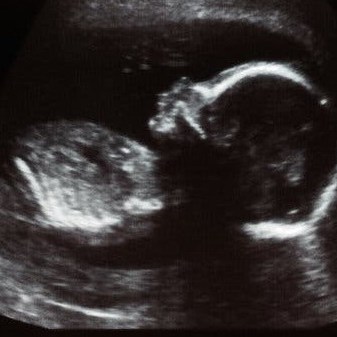

But behind the veneer of caring, there is little being done to drive the transformative change to move black bodies from being the object to the subject. We’ve heard the shocking statistics surrounding the stark disparities between the death rates in childbirth and pregnancy between white and black women; this unacceptable reality is one that strikes fear into the hearts of every black woman who becomes pregnant, so really we should be the frontrunners to talk about this right? Apparently not.

Soon after giving birth to her first child Esmé by caesarean section, Candice caught a dangerous infection which sent her into septic shock. Since then she has been at the forefront of discussing black women, childbirth and mortality.

With such a powerful perspective from her lived experience, Candice would have been the ideal candidate to tell the story of the harsh reality of the invisibility of black women, and how that has led to negligence rooting from unconscious racial bias. If Candice’s compelling and real delivery of her experience as a black mother in her book “I Am Not Your Baby Mother” is anything to go by, she certainly would have been the right person to lead the crusade for change.